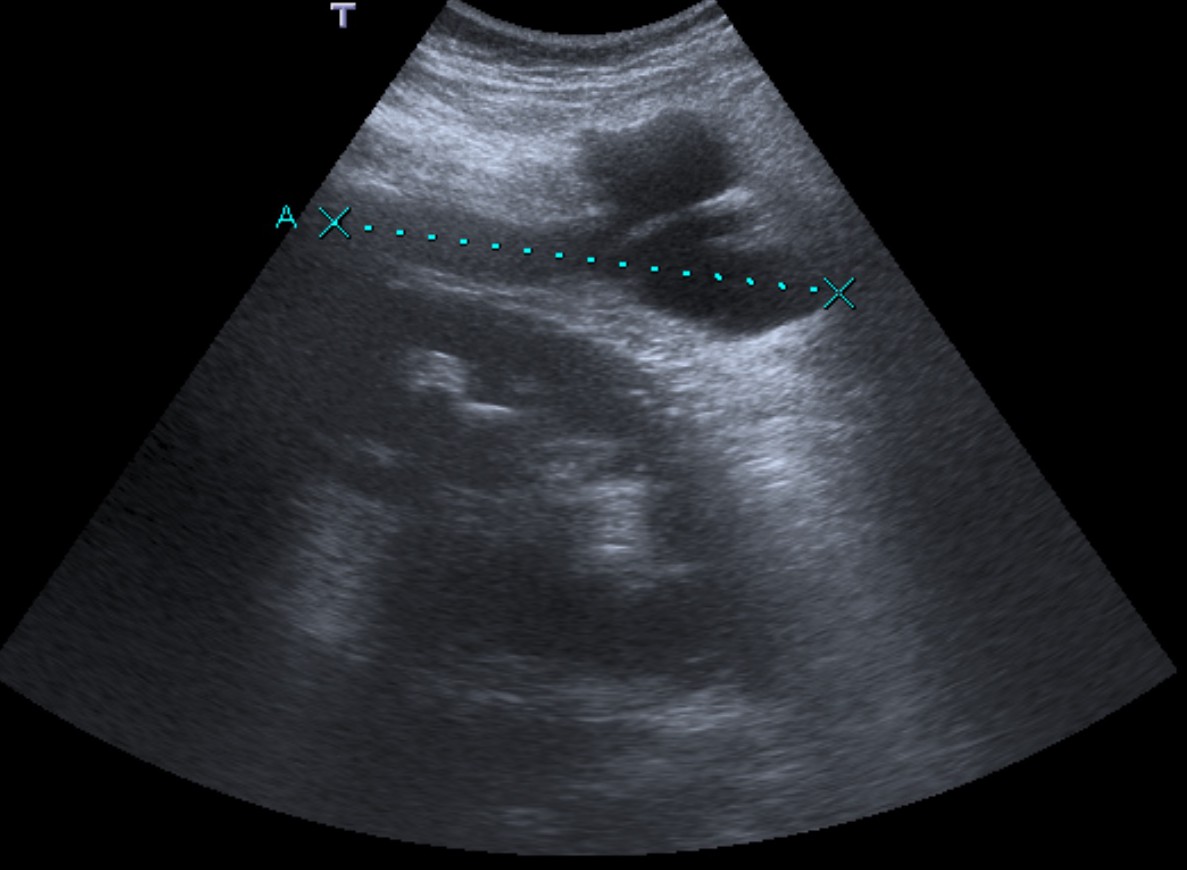

CASO 2: Paciente de 68 años con dolor en flanco izquierdo, fiebre y malestar general. A la exploración existe enrojecimiento de la piel con sensación de masa palpable y puño percusión muy positiva.

El paciente es alégrico al Iodo. Se realiza TC sin contraste para ampliar estudio.

Todos estos hallazgos están en relación con una Pielonefritis Xantunogranulomatosa que afecta al riñón derecho junto con una colección que ha fistulizado a región lumbar.

- Pielonefritis Xantunogranulomatosa.

- Es una forma infrecuente de pielonefritis crónica, de origen obstructivo, caracterizada por la formación de un absceso granulomatoso que puede extenderse al EPR-, severa destrucción renal y un cuadro clínico de fiebre, malestar general, dolor en el flanco y masa renal, a veces palpable.

- En placa simple podía verse un masa que renal con o sin borramiento de la línea del psoas. En ecografía, cálculos y aumento del tamaño renal en la forma difusa con múltiples áreas anecoicas correspondientes a las colecciones purulentas.

- Los hallazgos en TC pueden ser:

- Uni o bilateralidad de la lesión.

- Afección difusa o localizado.

- Litiasis de tipo coraliforme, calcificaciones intraparenquimatosas.

- Aumento difuso del tamaño renal.

- Áreas hipodensas o hipoecogénicas dentro de la lesión renal debidas a cálices dilatados, abscesos o áreas de necrosis parenquimatosa.

- Pobre o nula eliminación del medio de contraste en el riñón afectado.

- Compromiso inflamatorio que excede los límites del riñón y genera colecciones periféricas o extensión hacia vísceras vecinas.